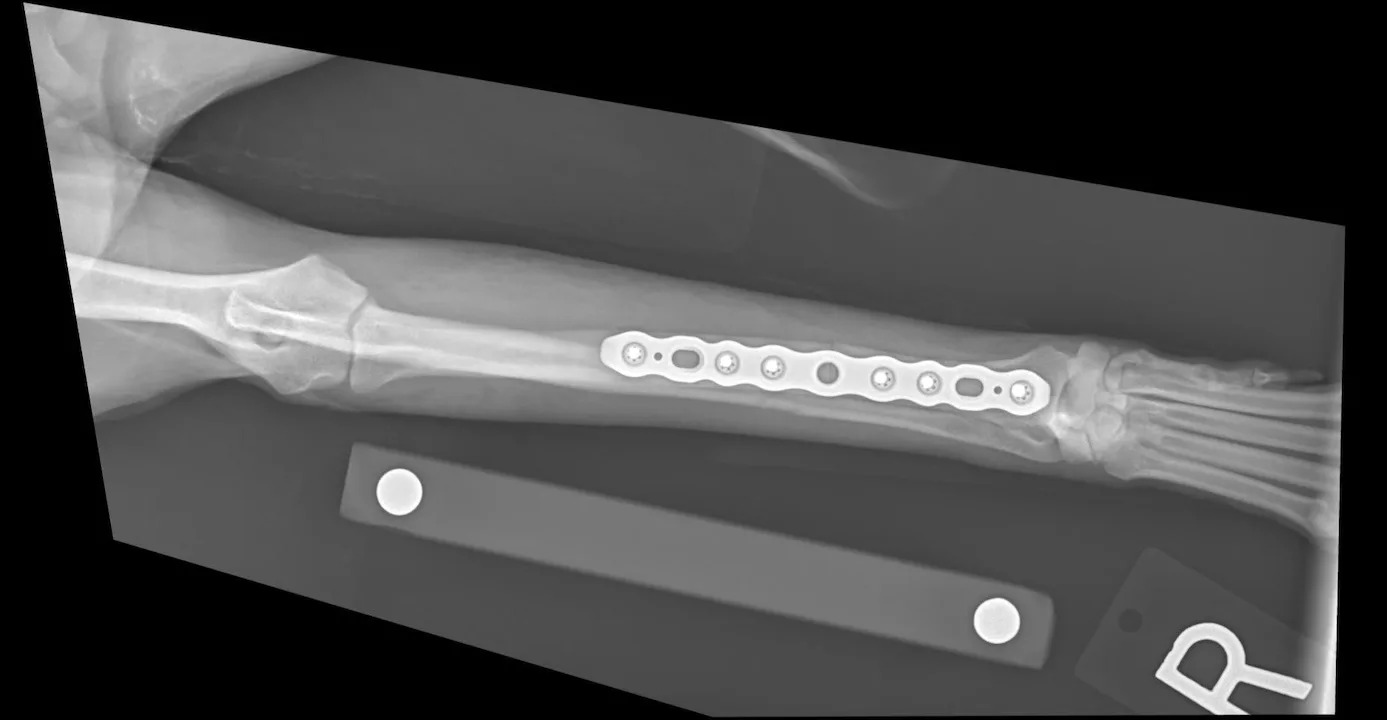

3. Plates & Screws

Bone plates are a highly versatile method of fracture repair. They can be used for any fracture that allows placement of 3 screws proximal and 3 screws distal to the fracture, engaging a total of ≥6 cortices.1 Plates can be applied in bridging, buttressing, or compressing configurations, depending on fracture configuration.1

The OrthoLine™ cuttable plate system is a versatile option that can accommodate a range of fracture patterns and anatomic requirements. Unlike most systems that require stocking multiple plate sizes and lengths, OrthoLine cuttable plates can be trimmed to the desired length, reducing inventory needs while maximizing flexibility. These plates are available in straight and T-shaped configurations, both allowing ≈7° to 8° of in‑plate bending before deformation. Sizes include 1.6 mm, broad 1.6 mm, 2.0 mm, and 2.4 mm. Although cuttable plates provide broad versatility, they are not available in all sizes needed for every patient or fracture type. The full OrthoLine system includes additional fixed-length plates and sizes that may be required to meet the needs of all breeds and fracture patterns.